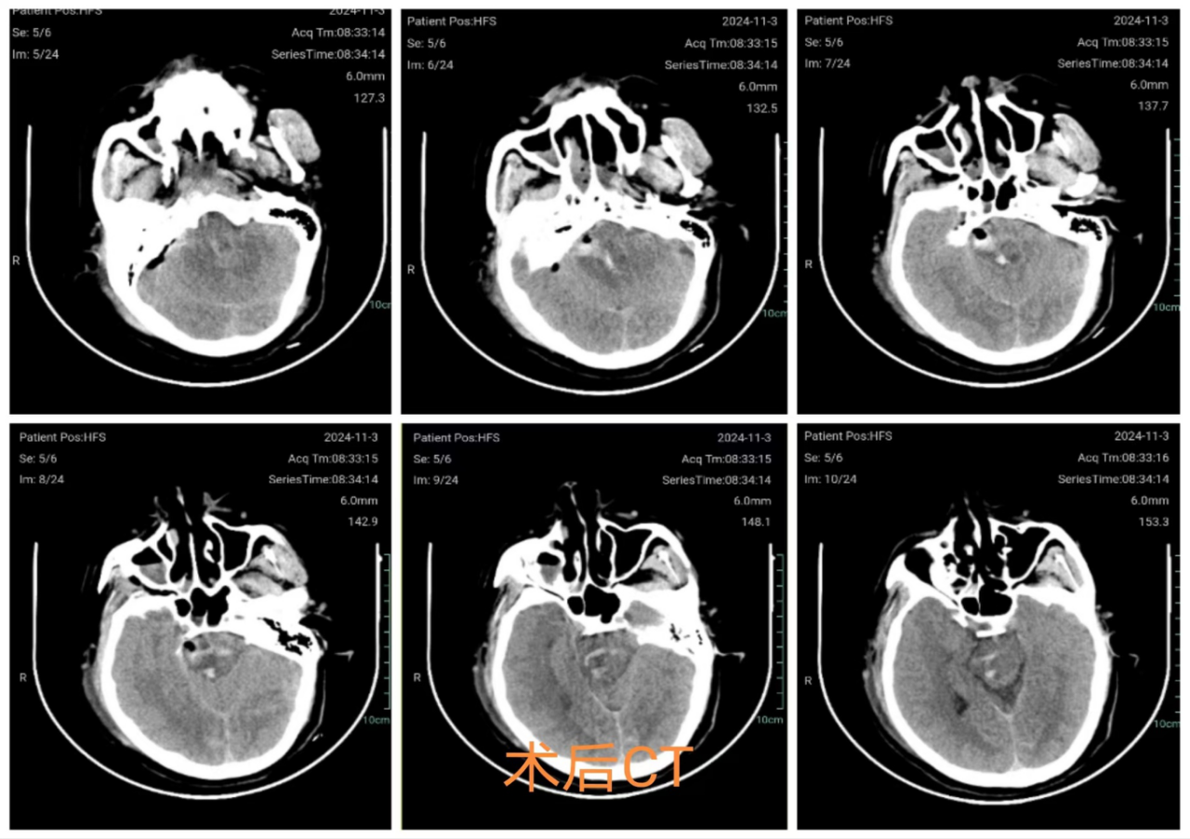

术后情况

术后第一天复查CT示脑干血肿清除干净,脑损伤不重

骨瓣2厘米,小于一元硬币